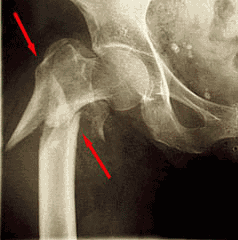

Een DHS wordt geplaatst bij een bepaald type “gebroken heupen”, wanneer het dijbeen (femur) breekt op het brede deel vlak voor de dijbeenhals (collum).

Men spreekt dan van een subtrochantere femurfractuur. De DHS of dynamic hip screw bestaat in feite uit twee componenten.We onderscheiden een stevige schroef die vanuit de laterale cortex van de schacht in de kop grijpt en een plaat die op de schroef aangrijpt en het geheel aan de schacht fixeert.

Het speciale kenmerk van een DHS is de mogelijkheid van de kop nagel om te glijden en dus te collaberen in de plaat. Dit is een enorm voordeel vanuit biomechanisch standpunt en voorkomt zeer vervelende en ernstige complicaties zoals “cut-out” en intra-articulaire perforatie van de schroef in het gewricht.